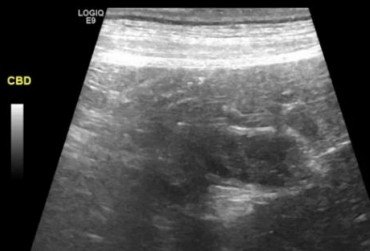

Pies, owczarek szetlandzki 6l. Mukocele. - 2

24 czerwca 2019

Wojciech Atamaniuk

Czytaj więcej

Pies, owczarek szetlandzki 6l. Mukocele. - 1